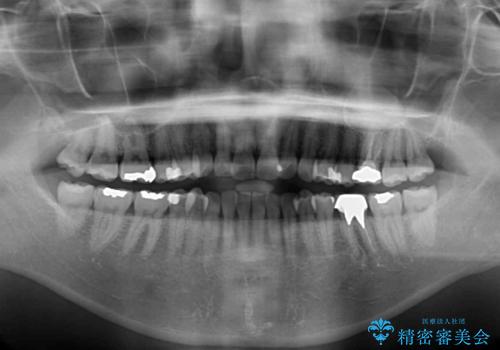

- 前歯のデコボコと上下スペースと前歯の隙間を気にして来院された患者様です。

目立たない装置を希望とのことでインビザラインにより、デコボコを解消しつつ、上下の前歯の隙間を閉じていくこととしました。

デコボコはあっという間に解消されましたが、上下前歯の隙間がなかなか解消されませんでした。

飲み込みの際に舌を前方に突出する癖があり、飲み込みの度に前歯に強く接触していたため、上下前歯の隙間が維持されていました。

舌の訓練を徹底していただいたことで、徐々に隙間は解消され、きれいな歯列に整えることができました。